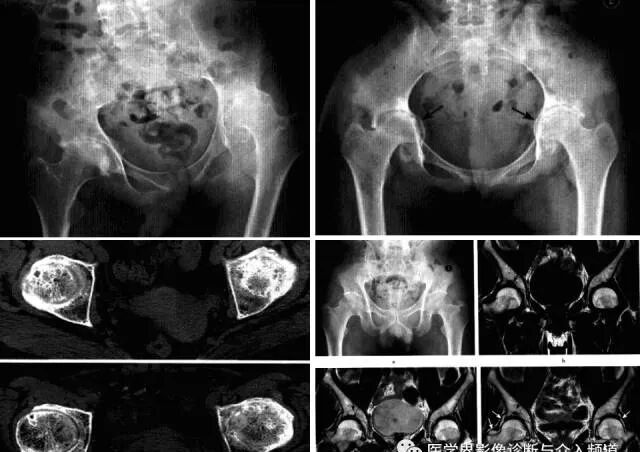

髋关节色素沉着绒毛结节性滑膜炎

一种侵及关节、腱鞘、滑囊或肌腱组织的良性增生伴色素沉着性病变。一般单关节发病,*常累及膝关节,其次是髋关节、踝关节、肩关节、肘关节。

病理:表面凹凸不平,有绒毛状滑膜皱襞覆盖,累及关节囊及周围软组织内血管和神经结构。

临床表现:以20-40岁青年女性多见,多有髋部外伤史,早期无特征,进展缓慢。

影像诊断:早期诊断缺特异性,晚期出现典型骨质破坏。MRI检查具较强特异性及定性诊断作用。